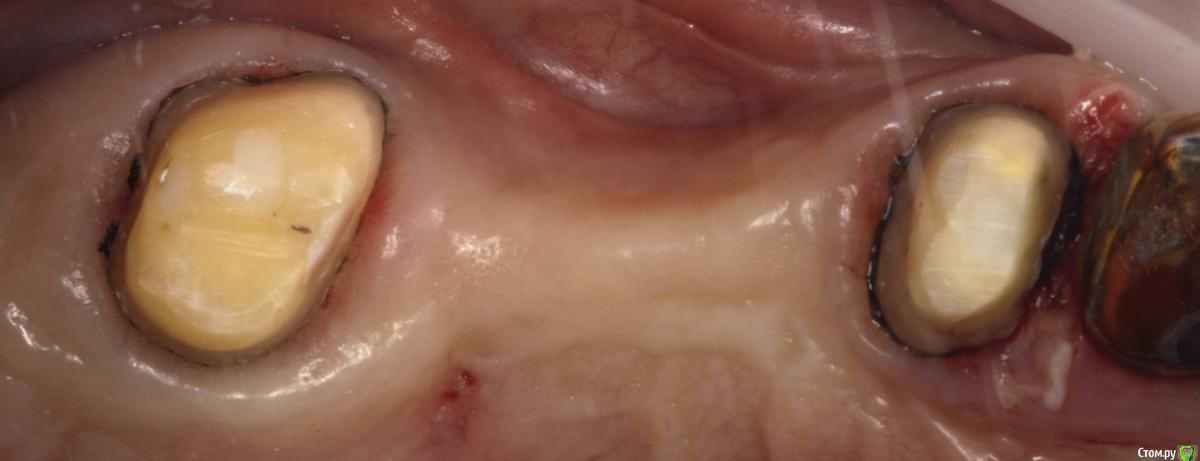

Rumata Опубликовано 19 октября, 2016 Поделиться Опубликовано 19 октября, 2016 Для оценки параллельности смотрите в зеркало приблизительно с 35 см одним глазом, ведете зеркало от зуба к зубу всегда под одним углом. Должны видеть весь уступ каждого отпрепарированного зуба. Но лучше, конечно, по отдельности все делать. 1 Ссылка на комментарий

M@estro Опубликовано 19 октября, 2016 Поделиться Опубликовано 19 октября, 2016 Было дело как-то. Препарирование в зеркало. Ссылка на комментарий